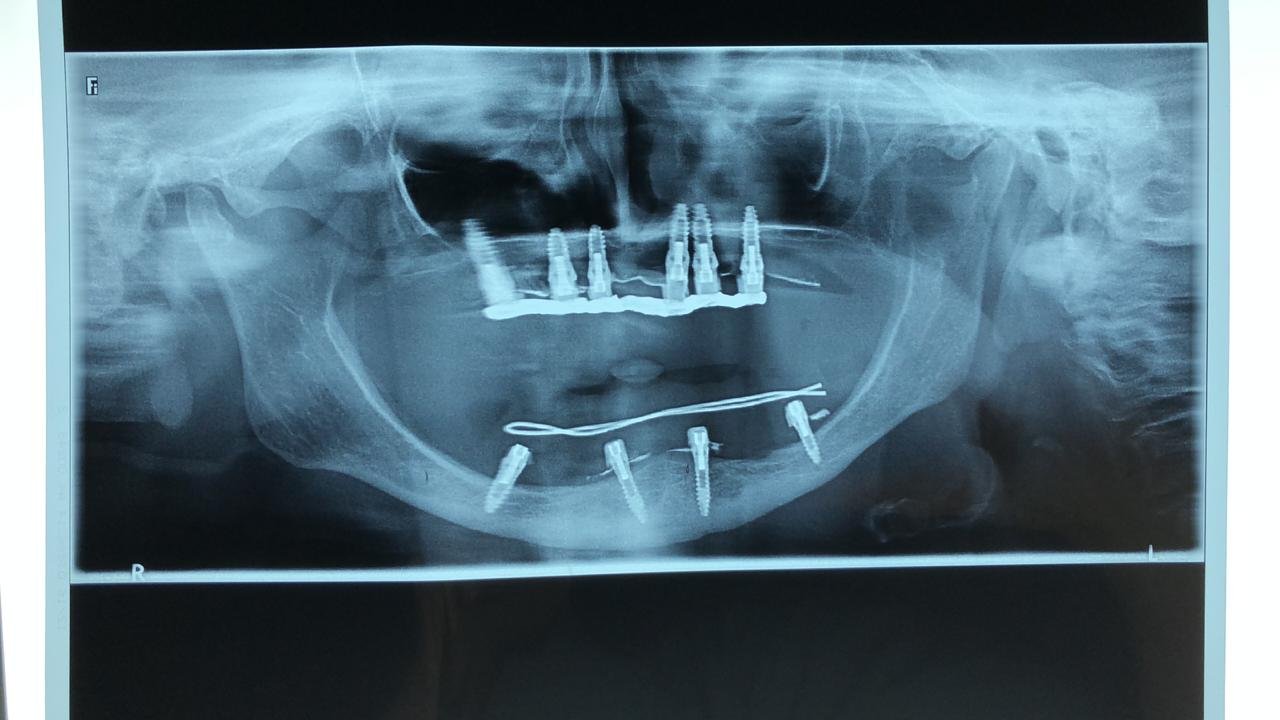

Implantes colocados en el 2004

La paciente se colocó en el 2004 los implantes ...ayuda porfavor necesito saber que sistema son para poder rehabilitarlos